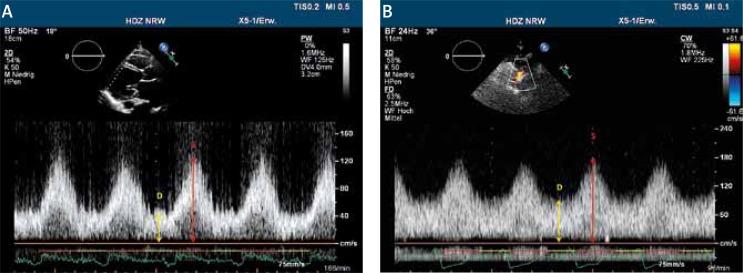

Here we present a patient after implantation of a left ventricular assist device (HeartWare) for destination therapy complicated by recurrent thrombosis of the device. At 14 months after implantation, the patient presented with a pump thrombosis after an INR incompliance period. A surgical pump exchange was performed and the patient recovered uneventfully. Five months later a pump thrombosis occurred again, and the patient refused surgery. Systemic thrombolysis was carried out this time. Three and 6 months later the same clinical picture was presented again, and repeat thrombolysis was performed successfully. The patient was discharged and has remained stable since, without any symptoms of thrombosis of the device.

在此,我们介绍一位接受左心室辅助装置(HeartWare)植入以进行终末期治疗的患者,该患者出现了装置反复血栓形成的并发症。植入后14个月,患者在国际标准化比值(INR)未达标的一段时间后出现了泵血栓形成。进行了手术泵置换,患者恢复顺利。五个月后再次发生泵血栓形成,患者拒绝手术。此次进行了全身溶栓治疗。三个月和六个月后,同样的临床表现再次出现,再次成功进行了溶栓治疗。患者出院,此后一直保持稳定,未出现装置血栓形成的任何症状。